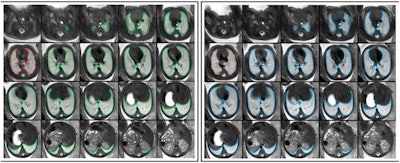

Repeated acquisitions of T2-weighted axial MRI images of the lung in a fetus at gestational week 32. 3D regions of interest (ROIs) encompassing the whole lung were manually segmented in initial (green) and repeat (blue) acquisitions of 30 fetuses. 2D ROIs were defined as lung segmentations at the level of the carina in initial (red) and repeat (orange) acquisitions, respectively. Radiomics feature reproducibility was assessed between features extracted from 2 and 3D ROIs in the initial acquisition (red vs. green), 2D ROIs in repeated acquisitions (red vs. orange), and 3D ROIs in repeated acquisitions (green vs. blue). Figure courtesy of Dr. Martin L. Watzenboeck, Dr. Florian Prayer, et al, and Insights into Imaging.Fetal MRI radiomics features extracted from 2D regions of interest (ROIs) do not adequately represent tissue characteristics of 3D ROIs encompassing the whole lung, the fetal imaging team in Vienna noted in an article posted on 8 February by Insights into Imaging. In addition, they exhibit insufficient reproducibility between repeated standardized fetal MRI acquisitions.

In contrast, a majority of fetal MRI radiomics features extracted from 3D whole lung segmentation masks are fully reproducible, the authors wrote.